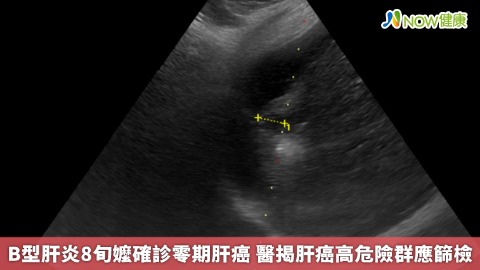

1986年前出生民眾有福 國健署推終身一次篩檢B、C肝

健康養生 / 生活保健4660為強化B、C型肝炎防治,國民健康署2025年8月1日起擴大成人預防保健服務B、C型肝炎篩檢年齡範圍,1986年以前出生至79歲民眾皆可終身接受一次免費篩檢。此措施將使220萬名青壯年族群可提早接受篩檢。 -

終結國病!健保允諾明年放寬B肝用藥 攜手擴大篩檢、力拚「功能性治癒」

醫藥衛生 / 保健專欄7980肝病為台灣國病,每年因慢性肝病、肝硬化及肝癌而死亡人數超過萬人,B型肝炎為主原之一,帶原個案超過200萬。健保允諾明年1月放寬B肝用藥給付規範,國健署則於今年8月1日推動擴大肝炎篩檢年齡政策,希望治療、預防雙管齊下,讓國人遠離肝疾死亡威脅。